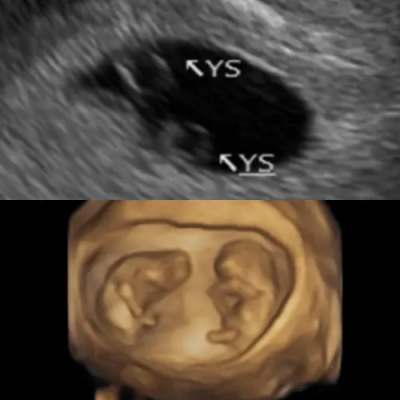

▲鄭家純分享孕肚超音波照,說明上圖為發現同卵雙胞胎的那一天,下圖是10週時所拍攝。(圖/鄭家純臉書)

令鄭家純驚喜的是,5週產檢時發現是雙胞胎,6週即聽到心跳聲,讓她眼淚瞬間往下掉,8週時確認是雙羊膜,安心很多,不過歷經過小產的鄭家純說,「從驗到兩條線到10週,心理上很難受,會亂想這次留得住嗎?懷雙胞胎真的沒問題嗎?」